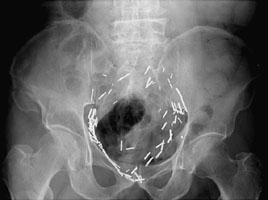

Duverney fractures are stable pelvic injuries. The fracture consists of an isolated fracture of one iliac wing. The pelvic ring remains intact although the patient is at risk for hemorrhage from the internal iliac arterial system. These fractures are caused by vertically directed forces.

- Click on the image for a larger versionAAP radiograph of the pelvis. This shows a comminuted fracture of the right superior iliac wing.